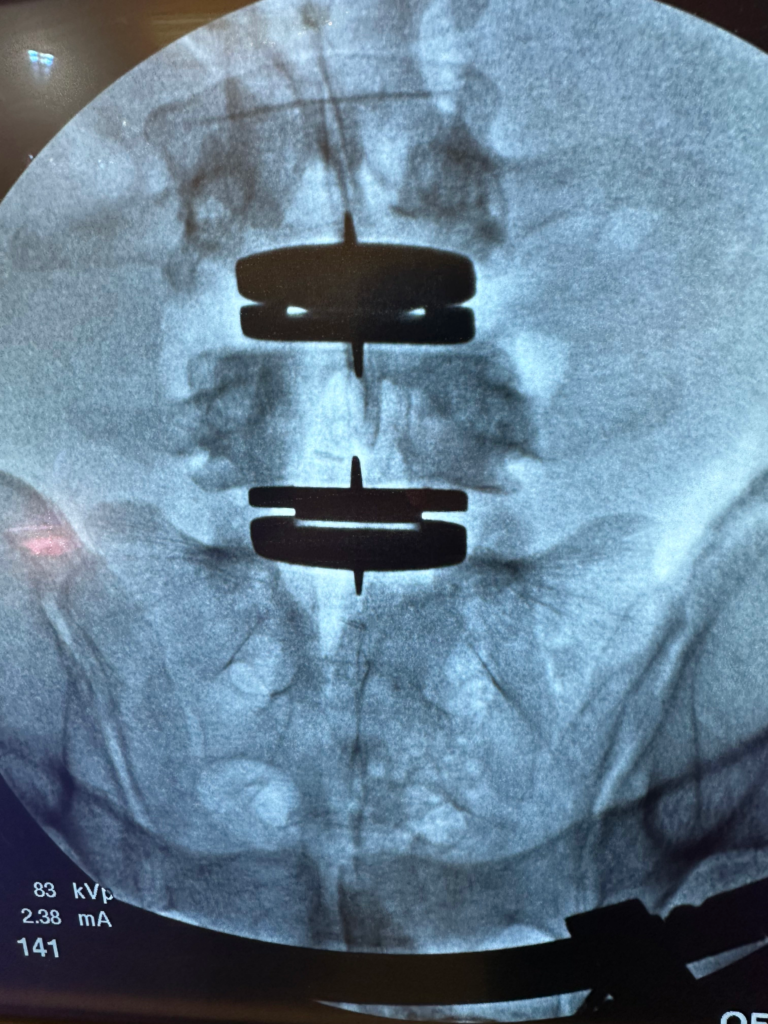

Lumbar disc replacement

Lumbar disc replacement

- Lumbar disc replacement